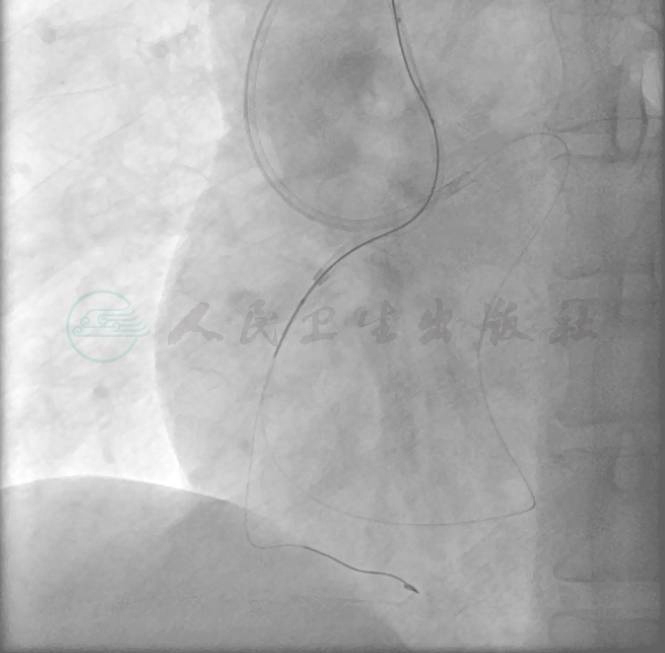

选择右侧桡动脉径路,6F 动脉鞘。造影显示:左主干未见异常,前降支中段偏心狭窄80%,回旋支中段狭窄70%,远段狭窄90%;右冠中段完全闭塞。左冠向右冠远端发出侧支循环(图1~图3)。

图3 右冠造影图